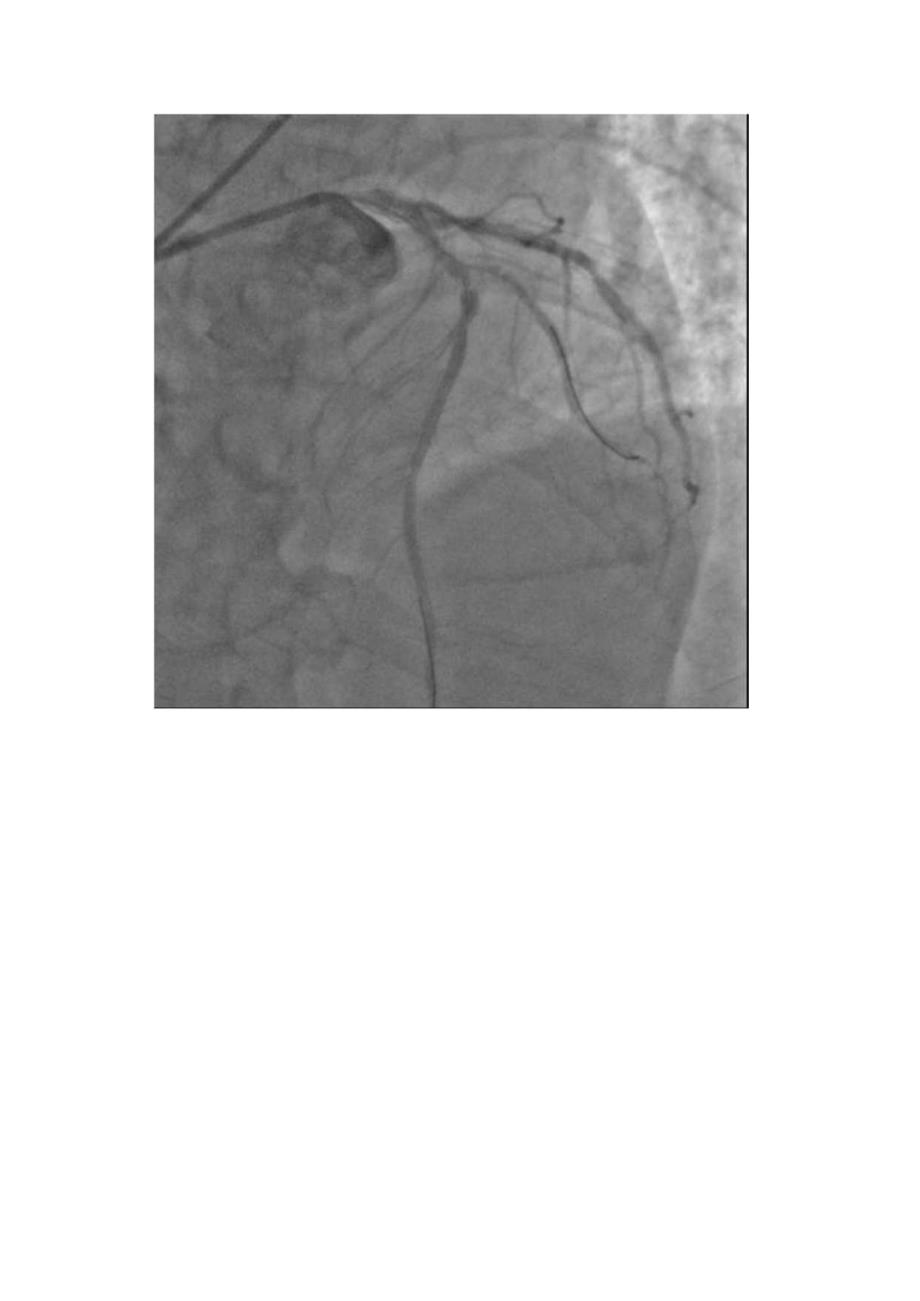

1、病史摘要:1.患者,男,66岁。2 .主诉:一周前突发胸痛8小时3 .查体:神志清,呼吸平稳,查体合作,应答切题。全身皮肤粘膜无黄染、皮疹、出血点。浅表淋巴结未及肿大。双瞳孔等大等圆,对光反射(+)。唇无绡。颈软,气管居中,颈静脉无怒张,甲状腺无肿大。两肺呼吸音清,未及干湿罗音。心前区无异常隆起,心率70次/分,律齐,心音可,未及额外心音,各瓣膜区未及病理性杂音,未及心包摩擦音。腹平软,无压痛、反跳痛及肌卫,肝脾肋下未及,移动性浊音(一),肠鸣音正常。双下肢无浮肿。神经系统(一)oBP12580mmHgo4 .辅检:突发胸痛8小时20130605新华医院崇明分院查心电图提示:窦律,异常Q波(V

2、I呈QS型,V2/V3呈qRS型)心肌损伤标志物:肌红蛋白500ngml,CK-MB35.8ngml,肌钙蛋白4.54ngml;48小时主治医师诊断:初步诊断:急性前间壁心肌梗死,killipI级初步诊断:急性前间壁心肌梗死,killipI级1.M:开口及近段狭窄60LAD:近中段弥漫性长病变伴钙化,最重狭窄95%,第一对角支开口及近段钙化伴最重狭窄85%:LCX:近中段弥漫性长病变,最重狭窄90%,远段狭窄65%,RCA:近中段长病变,最重狭窄80%,远段狭窄60%。目前诊断“冠心病,三支病变”,建议外科搭桥术拒绝,接受分次PCl术。介入治疗过程:对LAD病变血管行PCh经鞘管插入7FEBU